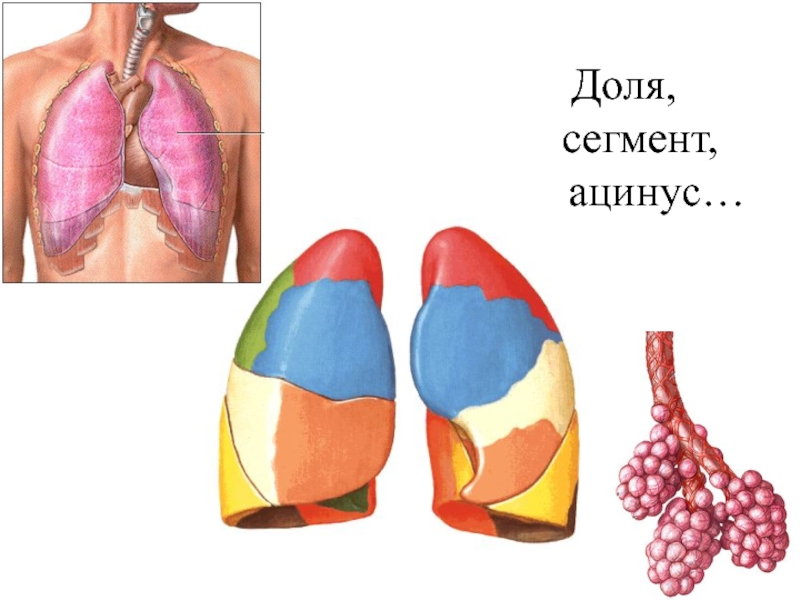

Анатомические изображения сегментов легких различных животных

Раздел: Другие животные